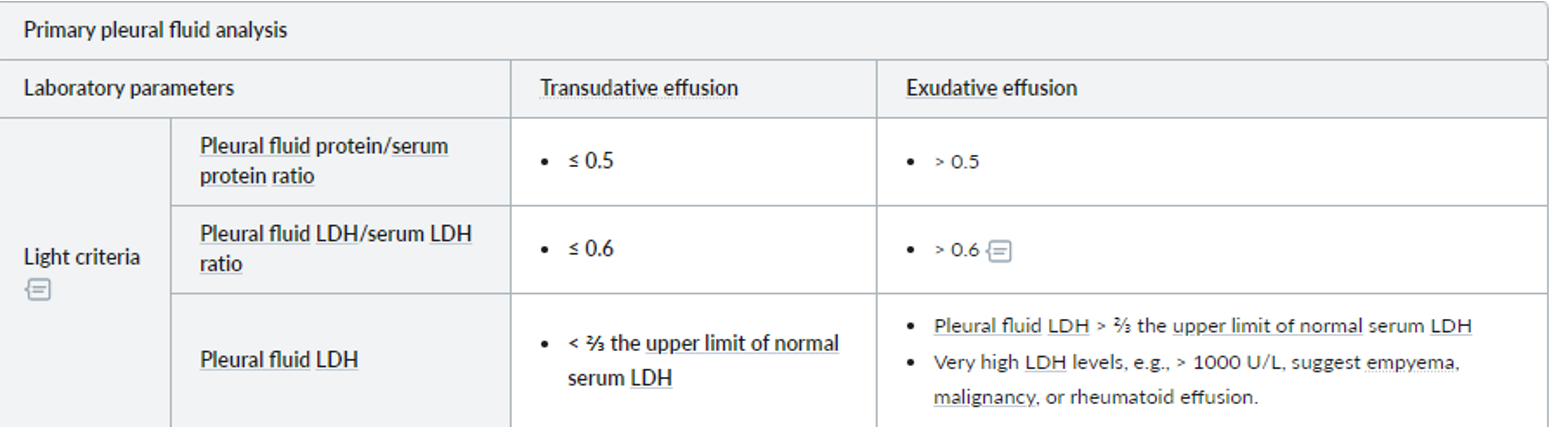

Pleural Fluid Analysis: Light Criteria - Differentiating Transudates from Exudates

- MEAT has low glucose: Malignancy, Empyema, Arthritis (rheumatoid pleurisy), and Tuberculosis are causes of pulmonary effusion associated with low glucose levels.

- Criteria for borderline cases:

- Exudates have a protein level of >30 g/L, transudates have a protein level of <30 g/L

- If the protein level is between 25 and 35 g/L, Light’s criteria should be applied.

The BTS recommend using the criteria for borderline cases:

exudates have a protein level of >30 g/L, transudates have a protein level of <30 g/L

if the protein level is between 25-35 g/L, Light’s criteria should be applied. An exudate is likely if at least one of the following criteria are met: